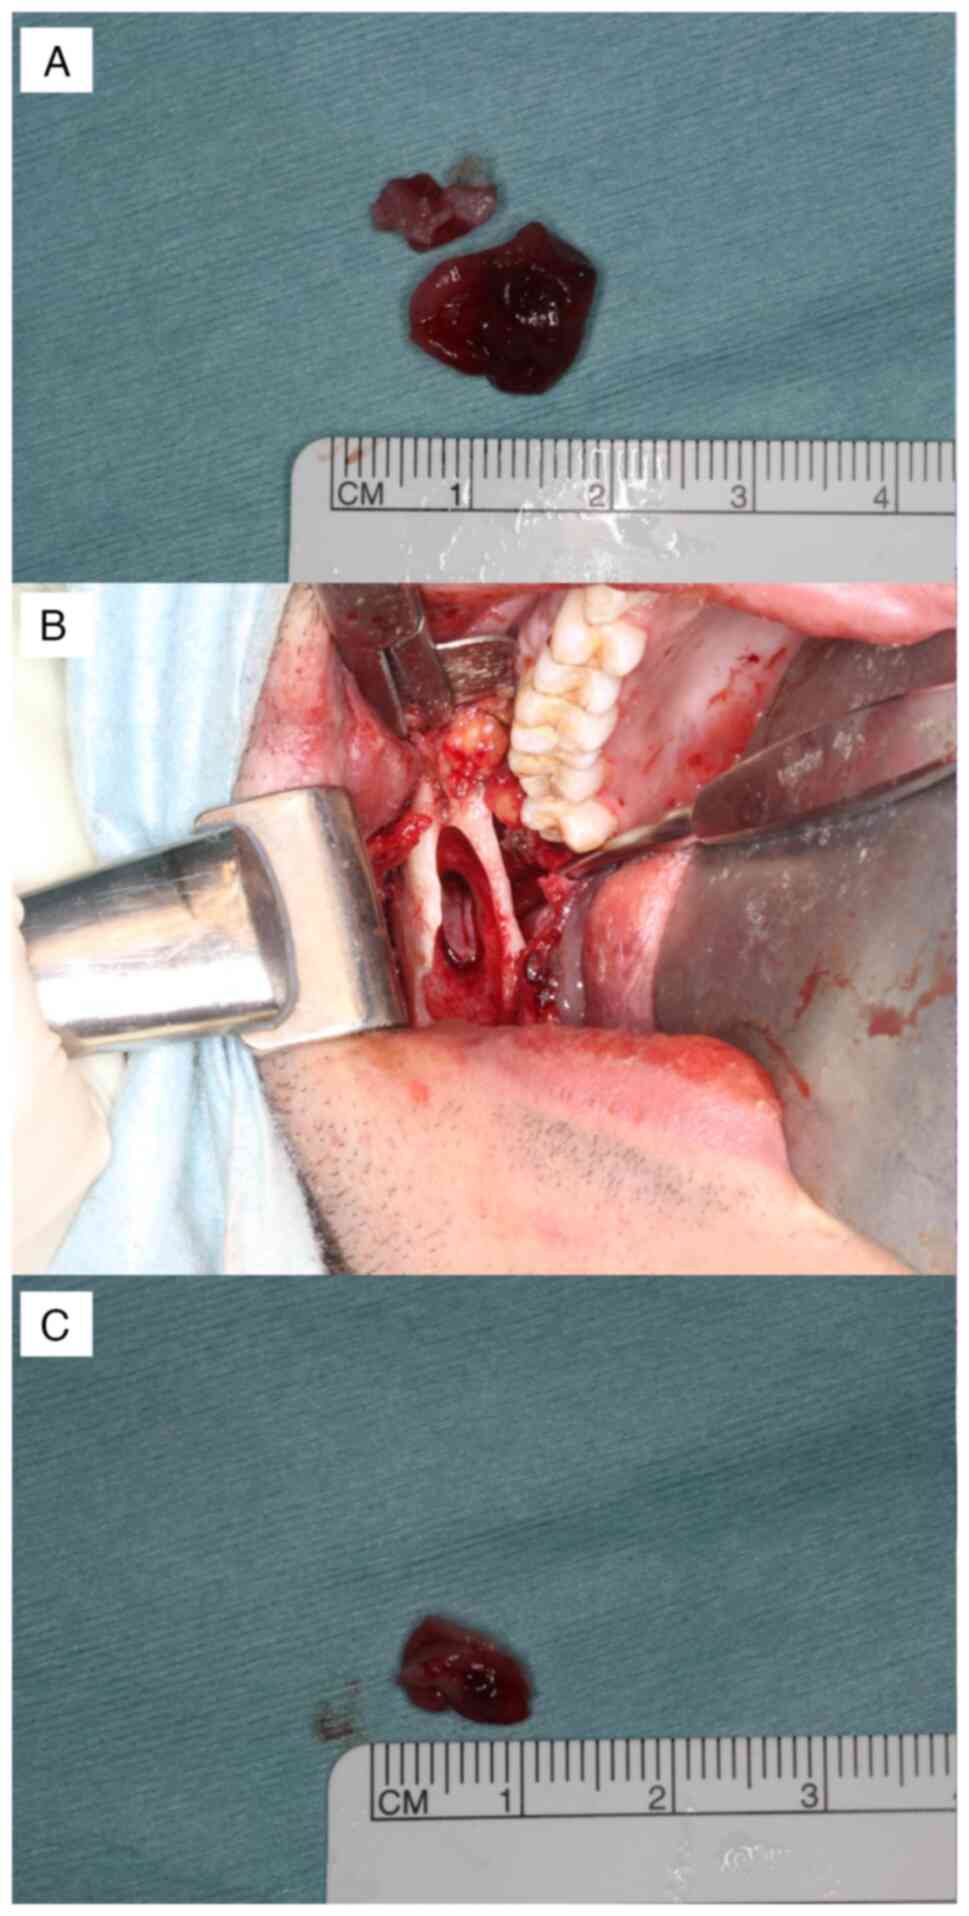

carefully detached. First, the anterior cyst left behind from the

anterior margin of the mandibular ramus was removed (Fig. 6A). After removing the anterior

head. An ultrasonic bone scalpel was used as needed. The posterior

cyst was confirmed and excised (Fig.

6B and C) after further

grinding of the surrounding bone to remove the daughter cyst, which